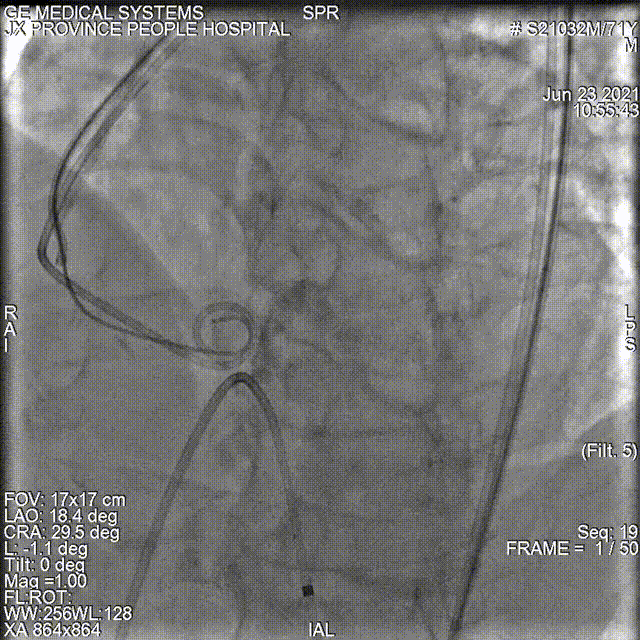

24型号VitaFlow瓣膜精准零位释放,

锚定位置良好。

此时造影显示偏少量偏中量反流,瓣膜形态欠佳,

考虑为瓣叶钙化过重,选择进行球囊后扩。